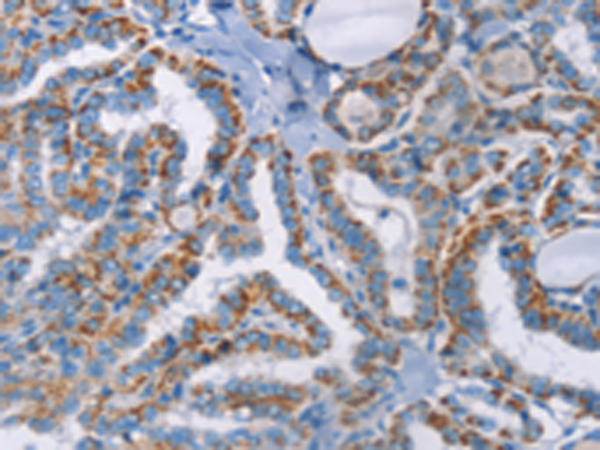

分类: 科研抗体货号: P07320别名: CSF; GMCSF应用: WB,IHC反应种属: Human